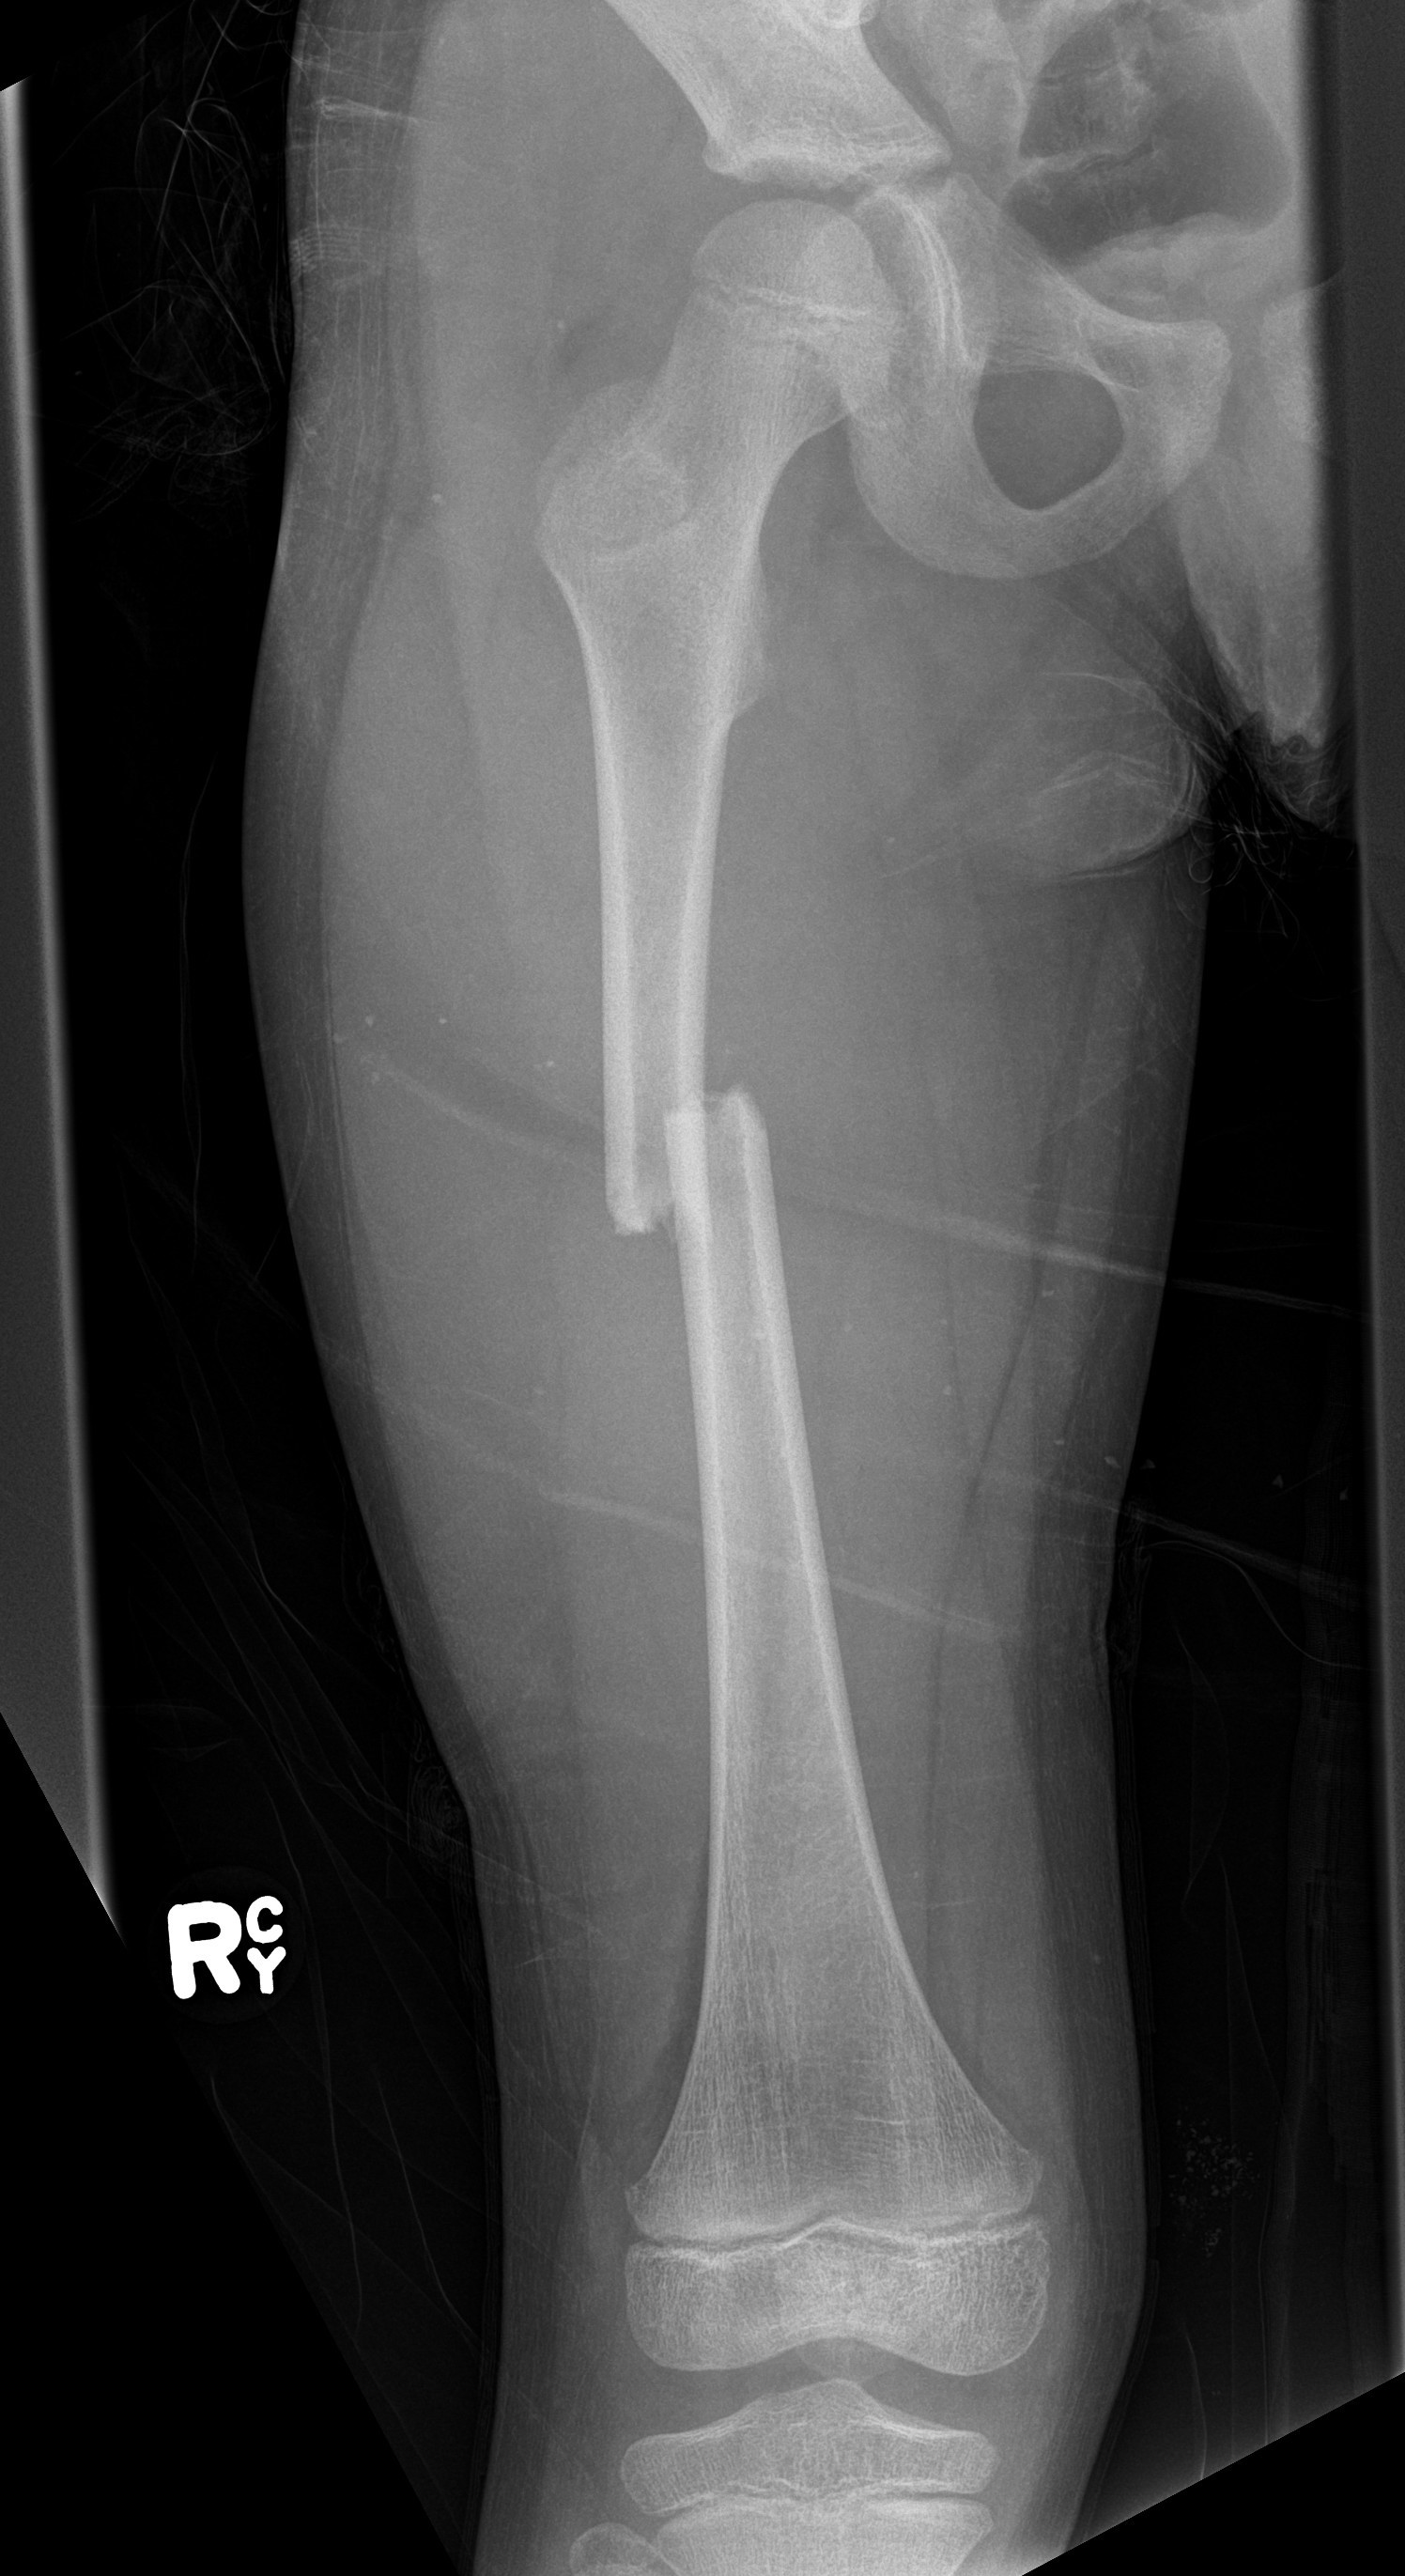

Flexible nails / Titantium Elastic Nails

Indications

Length stable fractures i.e simple transverse, short oblique

Midshaft fractures

Maximum weight up to 50 kg / 12 years old

Flexible nail technique

Wires

- available 1. 5 mm - 4.0 mm

- 30 - 40% of diameter of diaphyseal medullary canal

- i.e. if canal 10 mm wide, use 2 x 4 mm

- recommend using 2 wires same diameter to avoid rotational instability

Entry points

- medial and lateral insertion

- 1 - 2 cm proximal to distal femoral physis

- oblique entry with awl in direction of nail insertion

- can open with drill bit

- beware proximity of the femoral artery medially

- entry points should be symmetrical

Wire passage

- bend wire for 3 point fixation with bend at fracture site

- also bend the tip of the wire

- can use F Tool to reduce fracture / sheet in groin

- may need small incision and open reduction

- medial entry wire will pass into femoral neck

- lateral wire will pass into greater trochanter / medial wire into femoral neck

- use designated TEN wire cutter to cut wires

- cut off, tap in slightly further, leave 1.5 cm out so can retrieve

- wires that are too prominent can cause bursa / limit flexion / pain / protrude through skin

Acceptable alignment

- 10o varus / valgus

- 15o flexion / extension

- 15 mm shortening